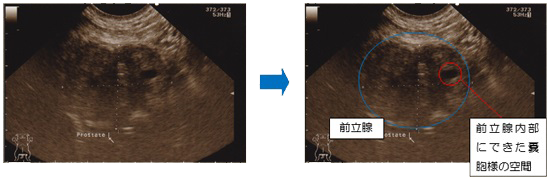

これは超音波検査の画像で6歳の男の子で未去勢の写真です。

前立腺はそれほど大きくはありませんが内部構造が正常の子より粗く、また嚢胞様の空間も見られます。

症状は見られませんが、今後去勢を行わないと病態が悪化し症状が出るかもしれません。